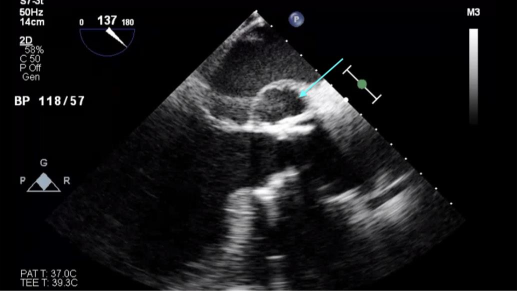

Transthoracic echocardiogram (TTE) showed a left ventricular ejection fraction of 30–35%. Transesophageal echocardiogram (TEE) revealed a mild-to-moderate anterior paravalvular leak of the bioprosthetic AVR and a pseudoaneurysm of the mitral-aortic intervalvular fibrosa (MAIVF) with communication to the left ventricle (Figures 1 and 2). No paravalvular leak had been identified on echocardiograms following his most recent AVR, and there was no evidence of pseudoaneurysm or paravalvular leak on prior TTEs or TEEs. The exact dimensions of the pseudoaneurysm were not documented in the report.